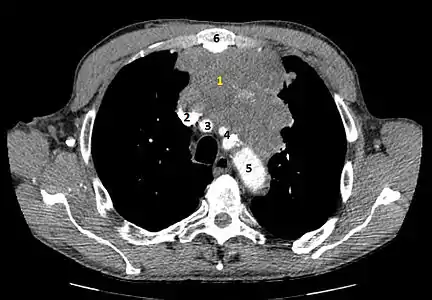

Le scanner thoracique est plus précis que la radiographie thoracique dans le diagnostic des thymomes, en raison d'une plus grande sensibilité envers les masses médiastinales. L'injection de produit de contraste iodé n'est pas forcément nécessaire, mais permet de préciser les rapports du thymome avec les structures vasculaires. Ceci permet à la fois la stadification et de préciser la stratégie chirurgicale lorsqu'elle est envisagée[28].

Les thymomes se présentent comme une masse bien définie du médiastin antérieur, proche du péricarde et dans un plan plus antérieur que les gros vaisseaux intrathoraciques (aorte ascendante et sa crosse, artère pulmonaire, veine cave supérieure). La masse peut être sphérique ou lobulée, mais présente un aspect homogène (plus rarement kystique) qui se réhausse après injection et peut contenir des calcifications[29].

Les critères scanographiques d'envahissement local doivent être recherchés car ils guideront le traitement. D'autre part, l'envahissement scanographique est corrélé au pronostic[30]. L'absence d'un liseré graisseux entre la masse et les vaisseaux, notamment l'aorte et la veine cave supérieure, est un signe d'envahissement local. L'ascension d'une coupole diaphragmatique, comme en radiographie thoracique, est un signe d'envahissement du nerf phrénique[31].

L'irrégularité des contours de la tumeur, ainsi que la présence de calcifications, de nécrose ou d'hémorragie intratumorale sont des signes de mauvais pronostic corrélés à des tumeurs plus agressives[32].

Scanner injecté, en fenêtre médiastinale, montrant un carcinome thymique envahissant les structures médiastinales :

1 : tumeur hétérogène, aux contours irréguliers, présentant des plages hémorragiques ;

2 : veine cave supérieure ;

3 : tronc artériel brachiocéphalique ;

4 : artères sous-clavière gauche et carotide commune gauche ;

5 : crosse de l'aorte ;

6 : sternum.